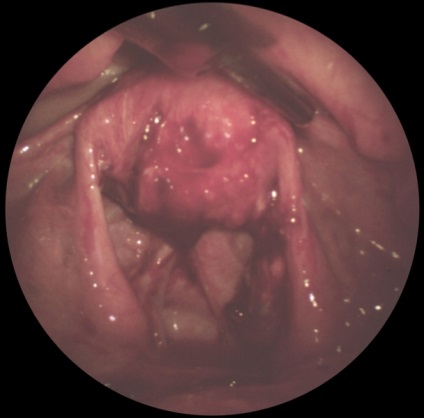

Laparoszkópia nőgyógyászat diagnosztikai és terápiás lehet előállítani bevezetésével laparoszkóp a hasfalon keresztül, vagy egy bemetszésen keresztül a posterior vaginális boltozatot (culdoscopy). Javallatok sürgősségi tartja az AL a nőgyógyászati gyakorlatban is gyanús petevezeték terhesség. piosalninks, apoplexia vagy petefészek ciszta, méh perforáció, és így tovább. d. A rutinszerűen elvégzett L. (culdoscopy) hosszan tartó kismedencei fájdalom ismeretlen etiológiájú, algomenoree súlyos, nehezen gyógyítható a szokásos orvosi terápiás módszerek gyanúja belső nemi rendellenességek és más szervekben. Contra L. hajtjuk a hasfalon keresztül ugyanazok, mint az L. vállalta, hogy vizsgálatát a hasüregbe. Culdoscopy ellenjavallt a súlyos összenövések pozadimatochnom térben a tumorokat a medence. Laparoszkópos kép savós petefészek ciszta ábrán látható. 4, valamint. Laparoszkópia is végezni néhány terápiás tevékenység: koaguláció és boncolása összenövések (. 4. ábra, b, c), endokoagulyatsiyu heterotopical gócok endometriumbiopszia petefészek punkció retenciós ciszták és mások.

Ábra. 4b). Laparoszkópos képet néhány nőgyógyászati betegségek - összenövések kismedencei folyamat.

Ábra. 4a). Laparoszkópos képet néhány nőgyógyászati betegségek - savós petefészek ciszta.

Ábra. 4c). Laparoszkópos képet néhány nőgyógyászati betegségek - orális forma kismedencei összenövések után laparoszkópos boncolás.